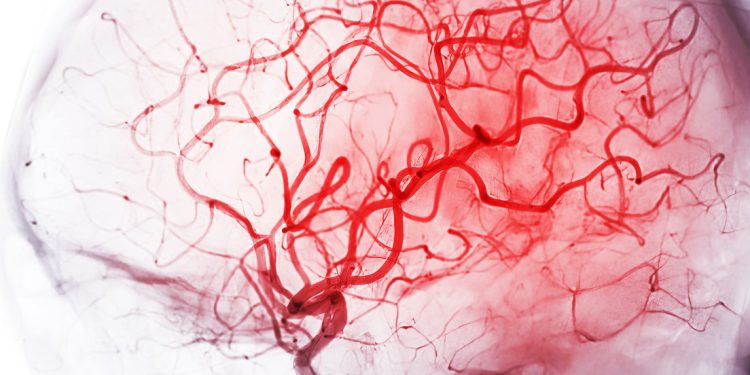

La relación entre la demencia y flujo sanguíneo cerebral ha cobrado nueva relevancia tras un estudio científico que identificó un posible mecanismo vascular clave en el desarrollo de esta enfermedad. Investigadores de la Universidad de Vermont descubrieron que restaurar un componente esencial en las células de los vasos sanguíneos podría normalizar la circulación cerebral y abrir la puerta a nuevas estrategias terapéuticas.

El hallazgo, basado en investigación preclínica, refuerza la idea de que la demencia no solo está asociada a proteínas anómalas o daño neuronal, sino también a alteraciones en la circulación que reducen el aporte de oxígeno y nutrientes al tejido cerebral.

Los científicos partieron de la hipótesis de que un riego sanguíneo defectuoso puede contribuir de forma directa al deterioro cognitivo. Según este enfoque, la falta de una circulación adecuada priva al cerebro de recursos esenciales para su funcionamiento normal.

En este contexto, el estudio analizó el comportamiento de las células endoteliales, responsables de regular el flujo de sangre en los vasos cerebrales y de mantener el equilibrio vascular.